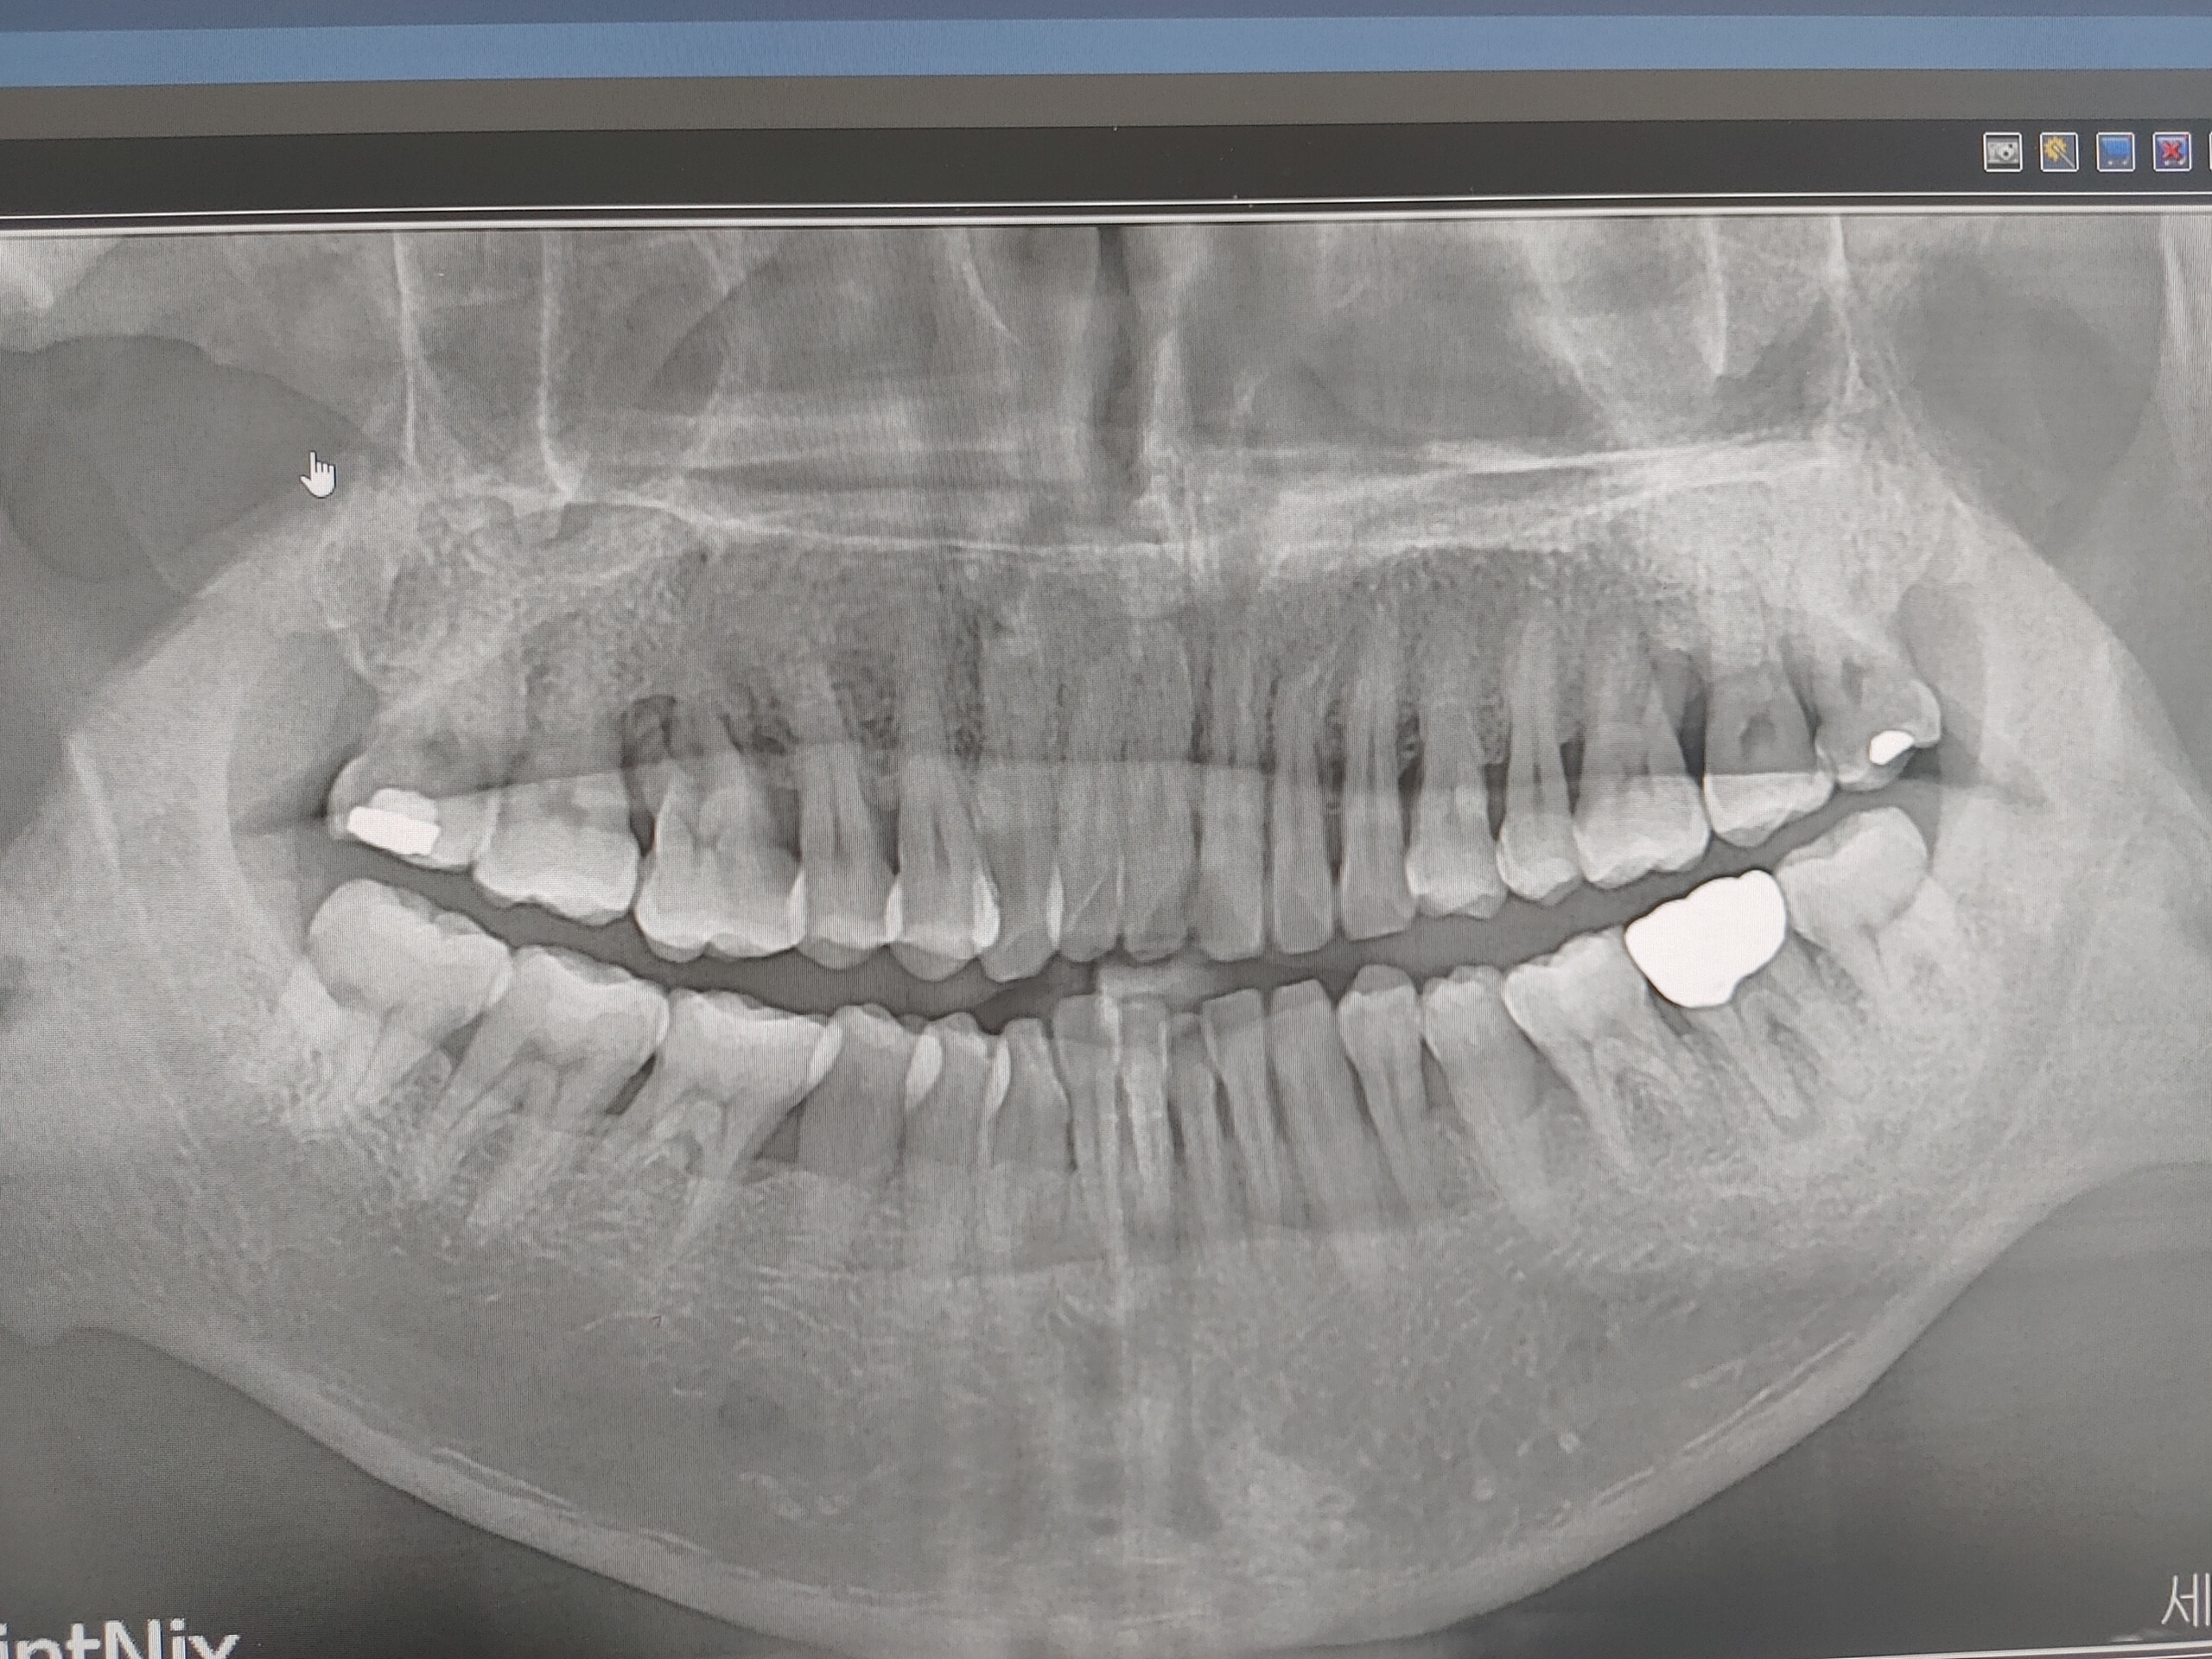

이 사진은 뿌리 밖고서 사진 찍었던건 같은데 @.@ .......

그 사진을 내가 찍었던거 같은게 정말 모르겠어요 ^^